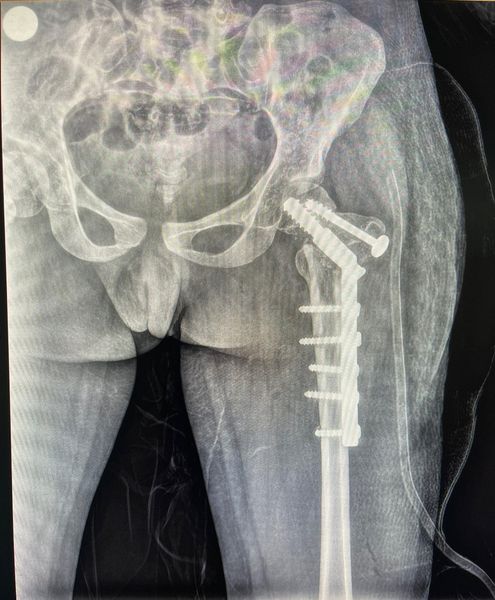

This one was corrected with Pauwel’s osteotomy and pediatric DHS fixation. Cancellous bone grafting was also done to the neck trochanter junction.